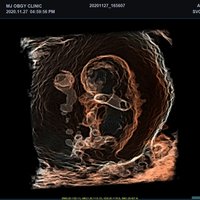

Mit dem X-CUBE 90 beginnt ALPINION eine neue Generation an Farbdopplersystemen, die X- CUBE Serie. Mit Bildverarbeitungstechnologien eines Premiumsystems und neuen Breitband- Schallköpfen mit X + Crystal Signature™ Technologie wartet das neue X-CUBE 90 auf.

Neben der hohen Bildqualität liegt ein weiterer Fokus auf der Vereinfachung und der Anpassung der Bedienung des Ultraschallgeräts. Individuell programmierbare Workflows und ein erweitertes Spektrum an automatisierten Messungen ermöglichen ein schnelleres und genaueres Arbeiten in jeder Situation.

eXpanded Capability

Das X-CUBE 90 bietet modernste Technologien für eine objektive und akkurate Diagnose. Intelligente klinische Module heben das System auf ein neues diagnostisches Niveau. Es erweitert Ihre Fähigkeiten und die Bandbreite Ihrer Möglichkeiten. Dazu gehören Module wie MicroView, point Shear Wave Elastographie (pSWE), oder auch die Kontrastmittelsonographie.